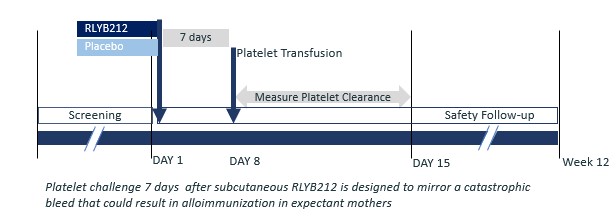

The Phase 1b single-blind, placebo-controlled proof-of-concept clinical trial was designed to establish the ability of SC RLYB212 to rapidly eliminate HPA-1a positive platelets transfused to HPA-1a negative healthy subjects. The study included 11 males aged 18 to 65 years, randomized to RLYB212 0.09mg (n=4), RLYB212 0.29mg (n=5), or placebo (n=2). We reported top-line results from this trial at the 31st Congress of the International Society on Thrombosis and Haemostasis ("ISTH") in the second quarter of 2023 and announced publication of the complete dataset in Thrombosis and Haemostasis in the third quarter of 2024. The results showed that SC RLYB212 administration produced a dose-dependent, rapid, and complete elimination of transfused HPA-1a positive platelets in HPA-1a negative subjects, with both doses meeting the prespecified proof-of-concept criteria of ≥90% reduction in mean platelet elimination half-life. Mean platelet elimination half-life was 5.8 hours (0.09mg dose) and 1.5 hours (0.29mg dose) for RLYB212 compared to 71.7 hours for placebo. Consistent with the Phase 1 first-in-human trial, RLYB212 was observed to be well-tolerated with no reports of serious or severe adverse events.

The Phase 1b single-blind, placebo-controlled proof-of-concept trial was designed to establish the ability of SC RLYB212 to rapidly eliminate HPA-1a positive platelets transfused to HPA-1a negative healthy subjects. The study included 11 males aged 18 to 65 years, randomized to RLYB212 0.09 mg (n=4), RLYB212 0.29 mg (n=5), or placebo (n=2). The study design and results are summarized below.

RLYB212 Phase 1b Trial — Design and Results